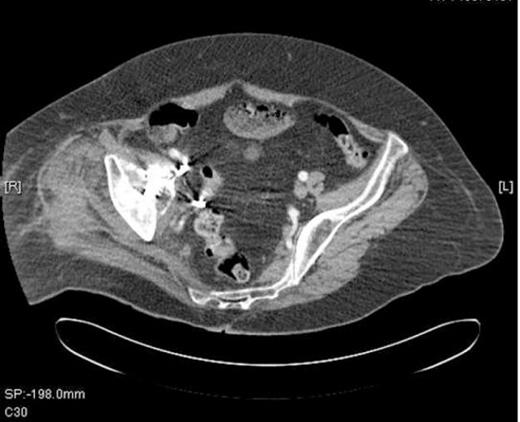

He was admitted to the High Dependency Unit for post operative recovery where he spent 6 days. On return to the elective ward, he made an uneventful recovery and required anticoagulation with warfarin for six months to protect the IVC filter. The most recent radiograph of his pelvis (Figure 4) showed excellent incorporation of the bone graft.